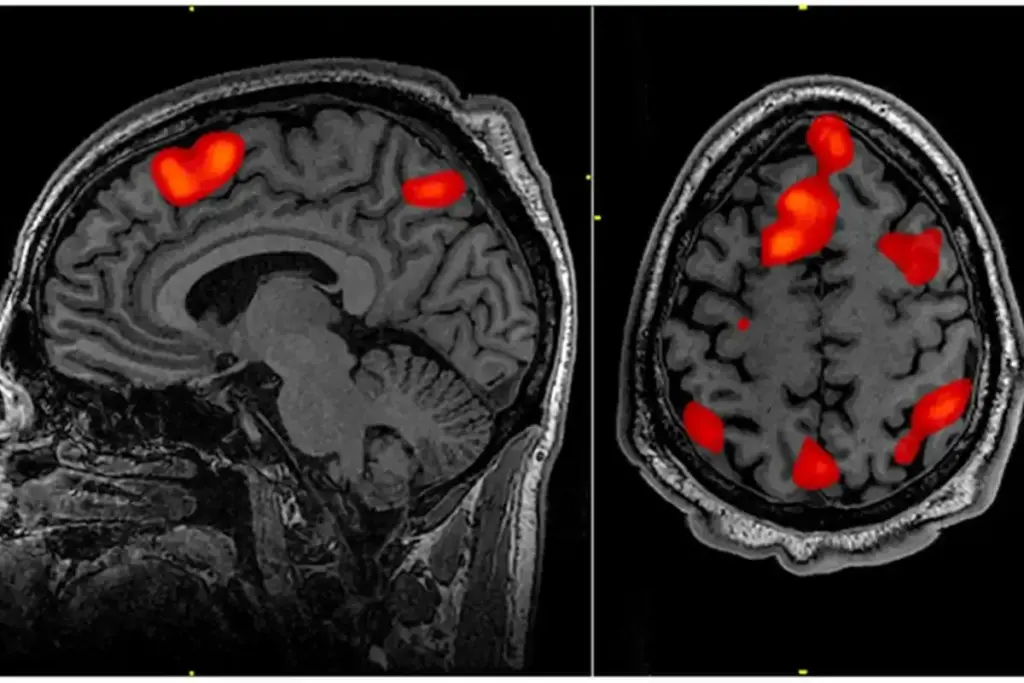

An MRI scan can show doctors the inner ear and nearby areas in great detail. This helps find out why you might be hearing these sounds. Knowing the cause helps doctors create a good treatment plan for you.

When Doctors Recommend an MRI for Tinnitus

Healthcare providers might suggest an MRI for tinnitus if they see certain warning signs. Tinnitus is when you hear sounds that aren’t there. It can mean there’s something wrong inside your body. An MRI helps doctors find out what’s causing the tinnitus, if it’s with other signs.

What an MRI Can Detect in Tinnitus Patients

An MRI scan can show what’s causing the ringing in your ears if tinnitus symptoms don’t go away. Tinnitus often points to a deeper health issue. An MRI can find the main cause.

Acoustic Neuromas and Vestibular Schwannomas

An MRI can spot acoustic neuromas, or vestibular schwannomas. These are non-cancerous growths on the nerve from the inner ear to the brain. They can lead to tinnitus, hearing loss, and balance issues.

Early detection is key to avoid more problems. An MRI is a good way to find these tumors.

Blood Vessel Abnormalities

Abnormalities in blood vessels, like arteriovenous malformations (AVMs) or vascular loops, can also cause tinnitus. An MRI can find these issues. They might be pressing on nerves or brain structures.

Multiple Sclerosis and Other Neurological Conditions

In some cases, tinnitus is a sign of multiple sclerosis or other neurological problems. An MRI can spot these conditions by finding lesions or damage in the brain and spinal cord.